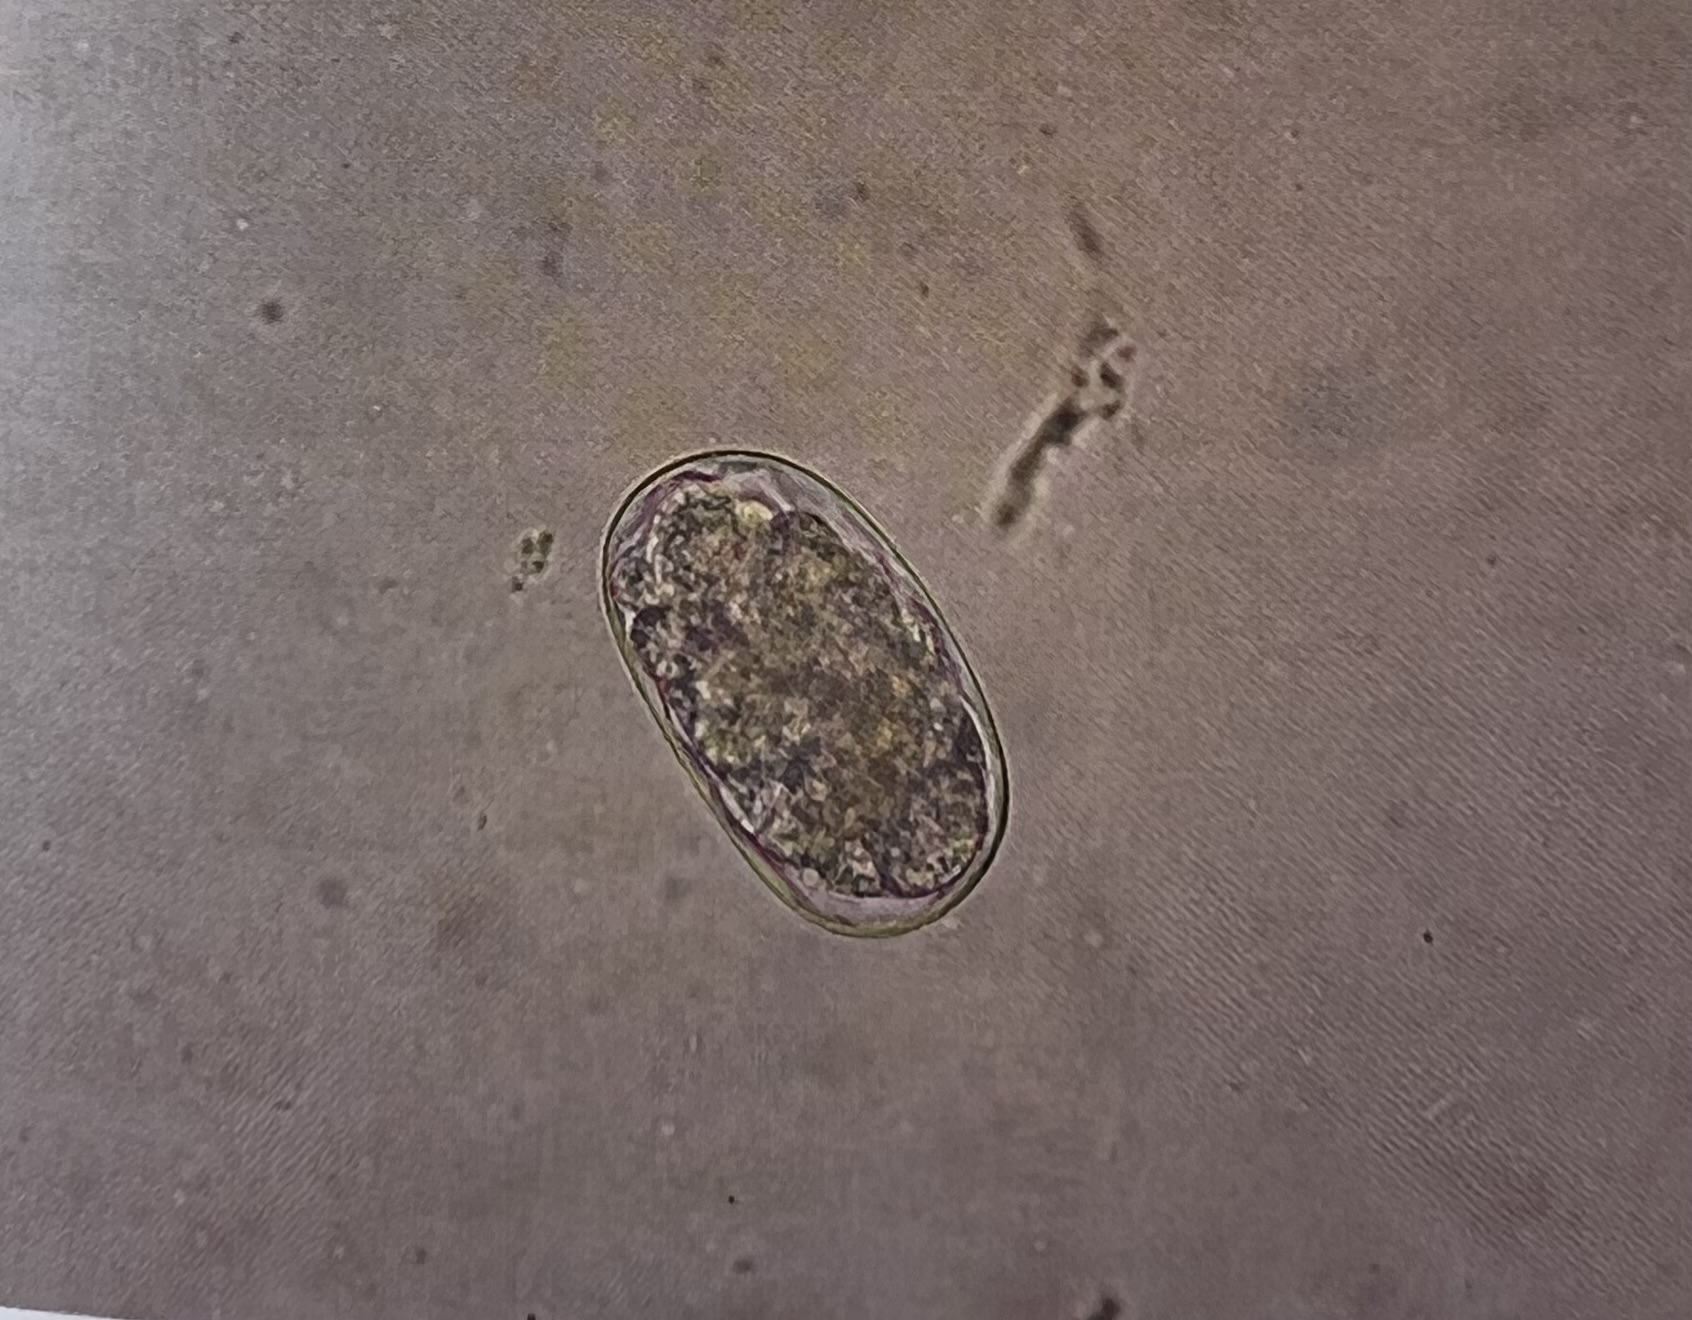

All hookworm eggs have an _____ shape.

oval

What egg is this? (common name)

hookworm